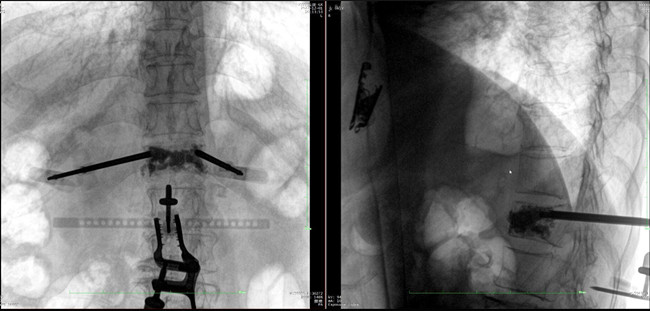

步驟二:手術(shù)實(shí)施

在病人體表切開一個(gè)長1-2cm的創(chuàng)口,沿骨科機(jī)器人的機(jī)械臂定位點(diǎn)方向?qū)⒖耸厢槍?dǎo)向套筒,通過創(chuàng)口送至病灶椎體處,并沿套筒方向打入克氏針進(jìn)行定位。沿導(dǎo)針插入工作套管,取出導(dǎo)針,完成球囊擴(kuò)張后,通過骨水泥注入器準(zhǔn)確地在骨折部位緩慢注入骨水泥,幫助其恢復(fù)椎體的形狀和強(qiáng)度。

? 手術(shù)效果確認(rèn)

*骨水泥置入效果良好